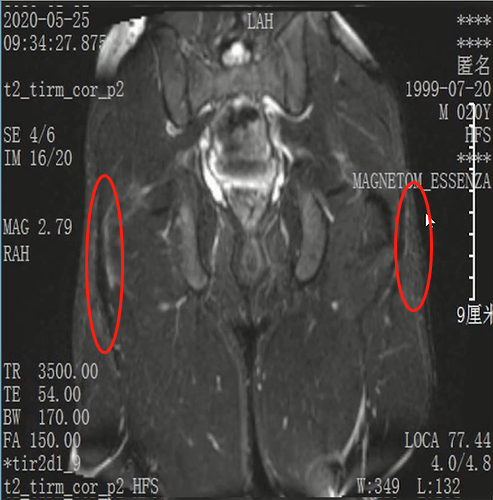

Lisfranc损伤在多发伤病人中常常容易漏诊,大约为 20-30%的漏诊率!